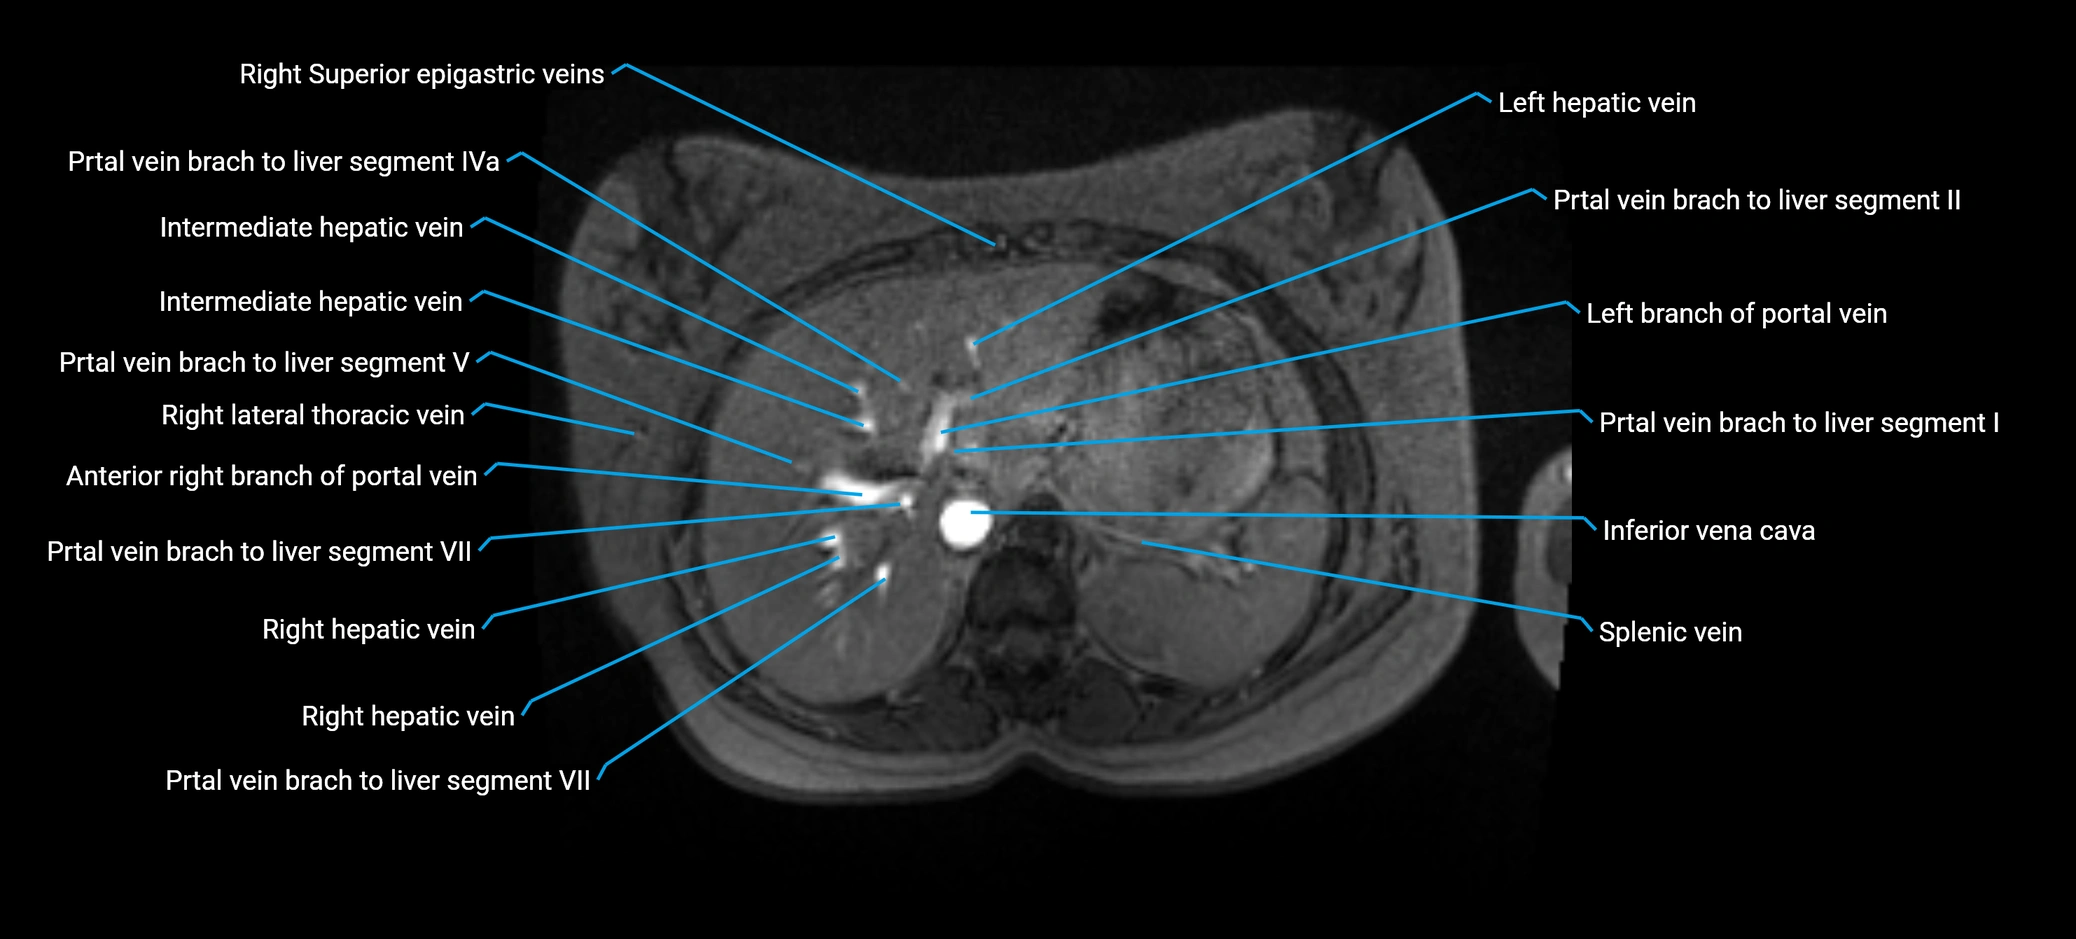

Anterior right branch of portal vein

The anterior right branch of the portal vein is a major intrahepatic division of the right portal vein. After the main portal vein bifurcates into right and left branches, the right portal vein divides into anterior and posterior segmental branches.

The anterior right branch supplies the anterolateral liver segments (Segment V) and anteromedial liver segments (Segment VIII) within the right hepatic lobe. It operates as a key vascular route delivering nutrient-rich portal venous blood to the central and superior right liver.

This segmental vasculature is of major importance in hepatic surgery, embolization, segmental resection, transplantation, and imaging-based liver segmentation.

MRI Appearance

MRV TOF (Time-of-Flight MR Venography):

• Appears as a bright, high-signal vascular channel representing flowing blood

• Clearly shows branching pattern of right portal vein into anterior and posterior branches

• Best in coronal or axial reconstructions for segmental mapping

• No need for contrast, relies on flow-related enhancement

MRI image

image